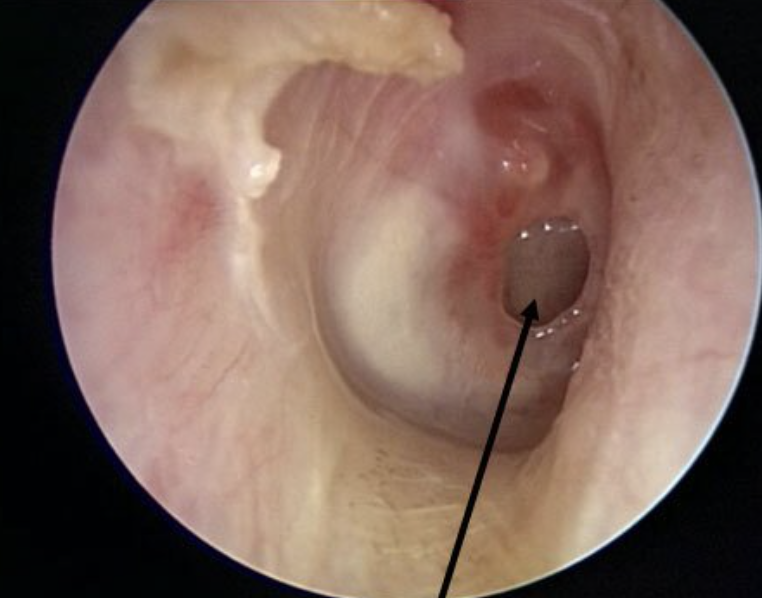

Perforated tympanic membrane

Ruptured tympanic membrane; a dark oval, hole will be present in the membrane

<p>Ruptured tympanic membrane; a dark oval, hole will be present in the membrane</p>